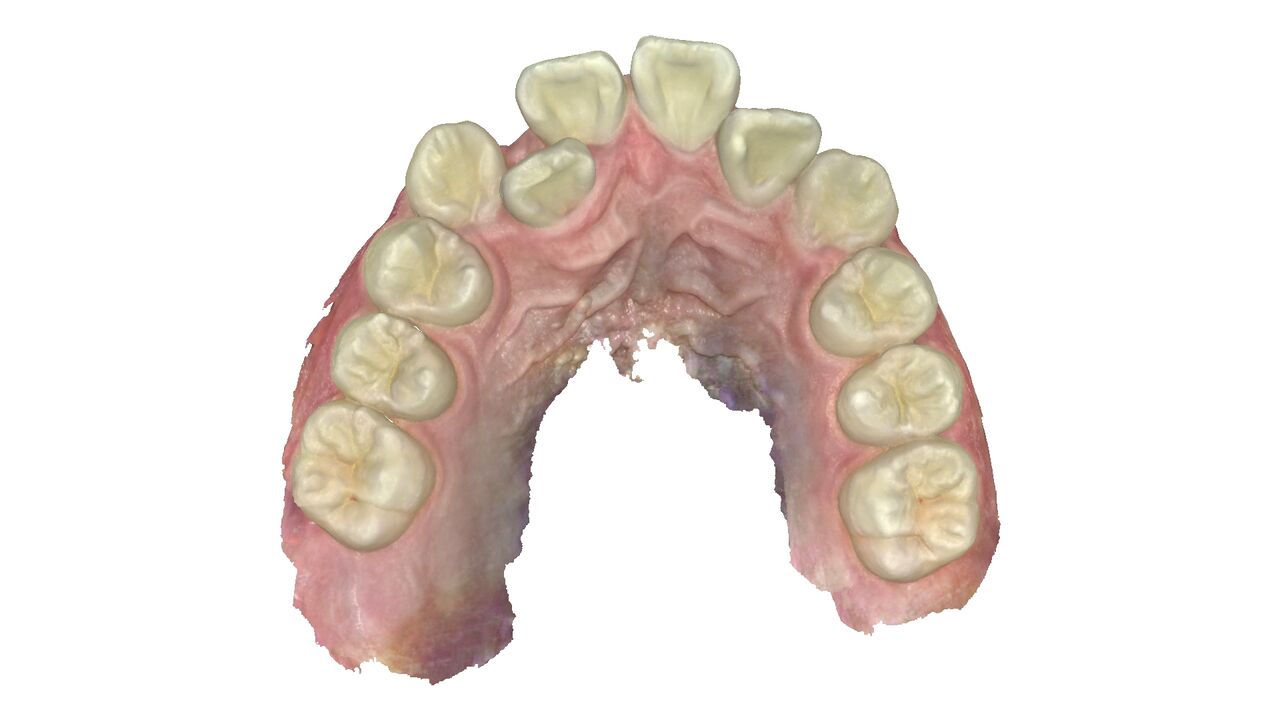

噛み合わせの比較。

患者さんは平成23年生まれの13歳とあごの成長が残っている世代だった為、あごの成長をコントロールすることもできわずか10か月で終了することができた。